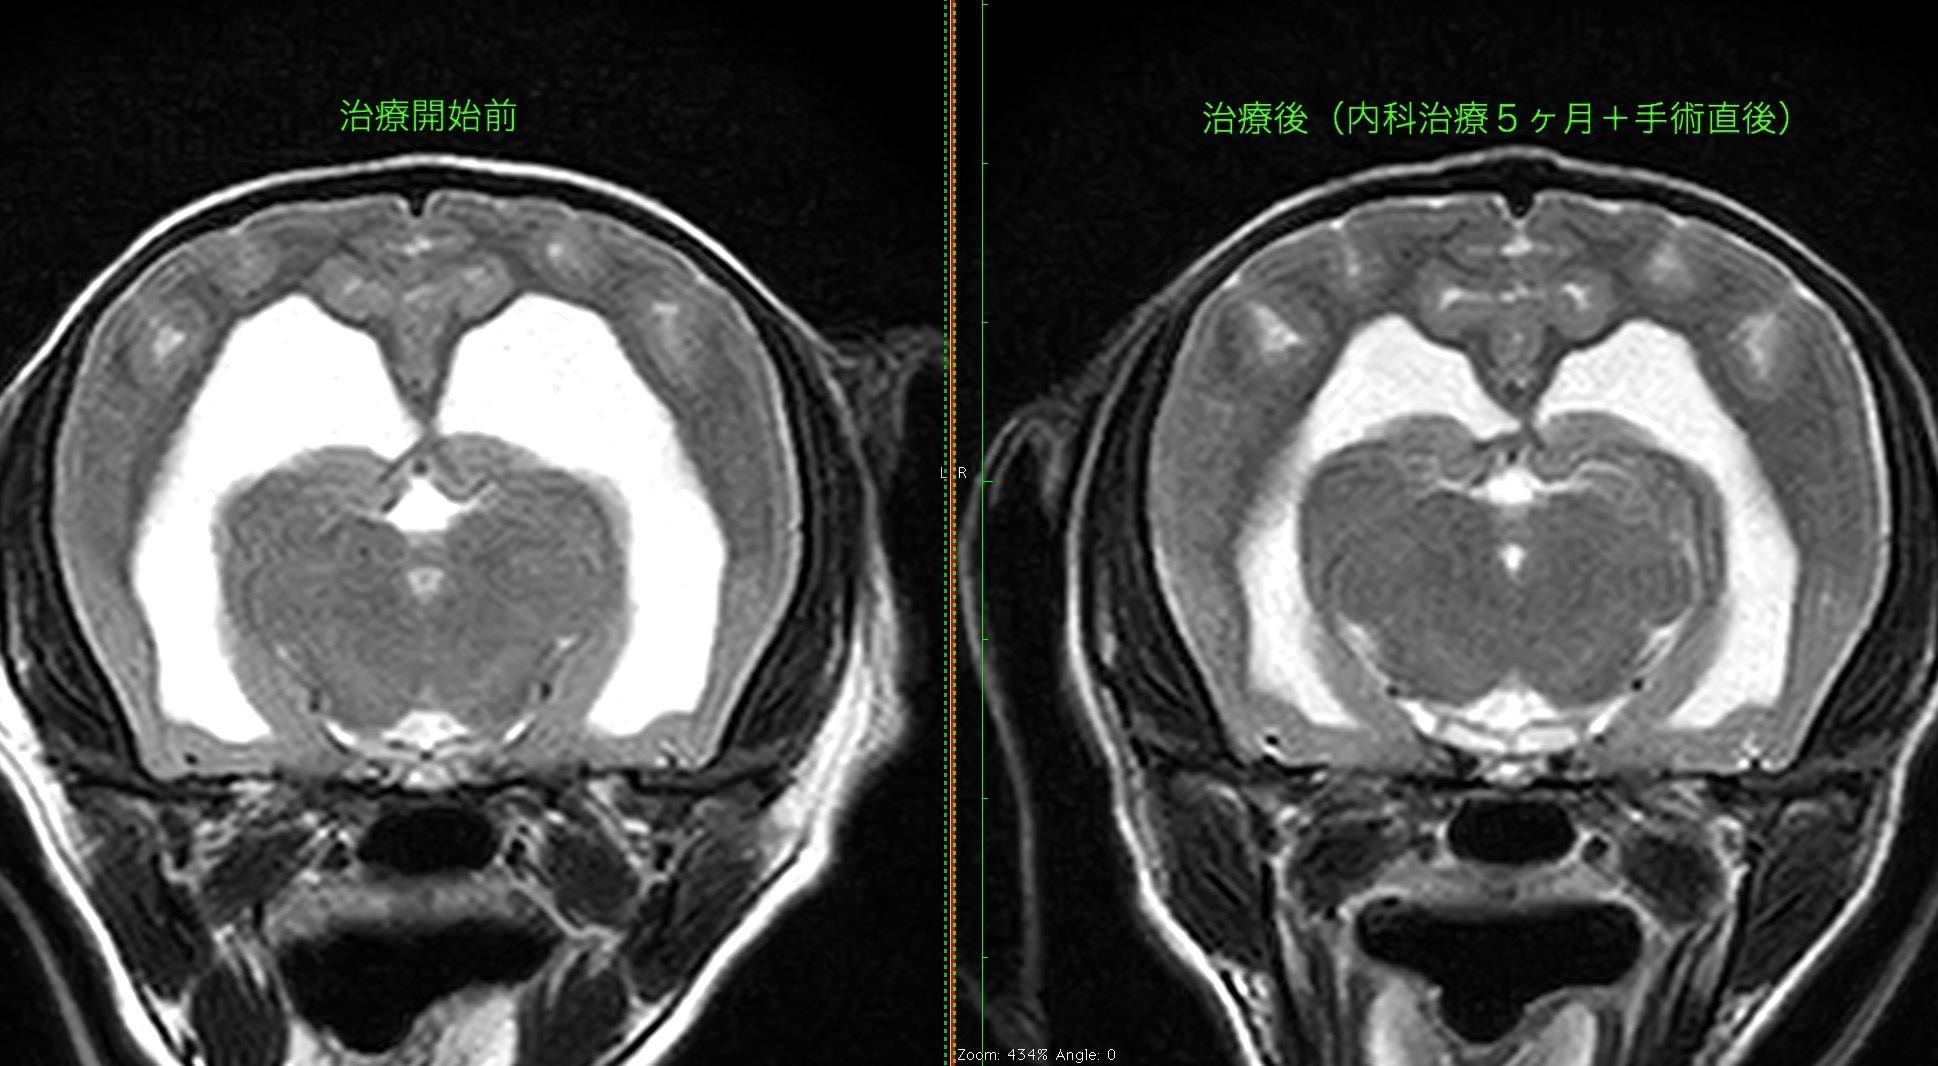

術前と術後のMRI所見(Axial) 両側側脳室拡張の改善が認められました。